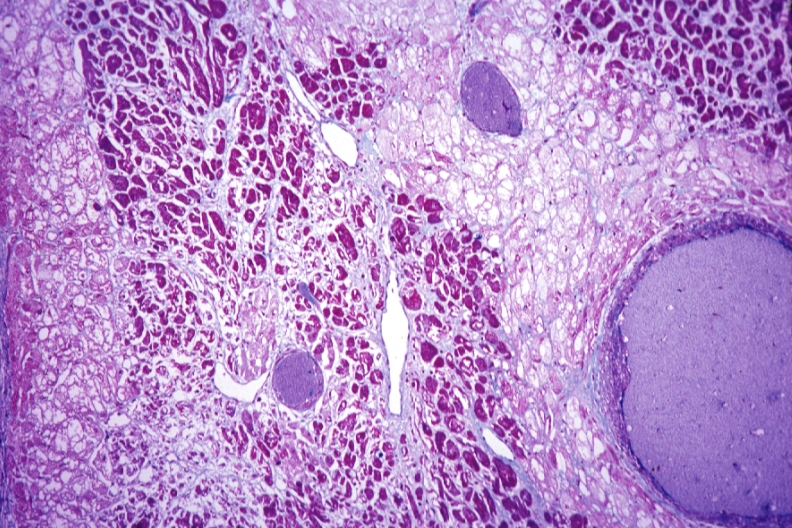

HISTOLOGY: CARDIOVASCULAR: HEART: Chronic Ischemia: Micro ald fusch high mag subendocardial myocytolysis and extensive myonecrosis same as slide 92